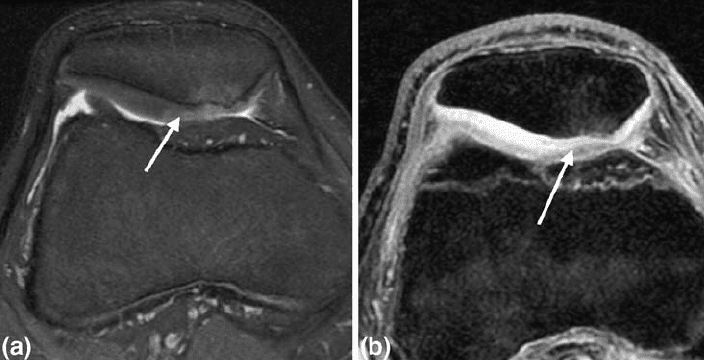

The healthcare professional may also ask for any of the following tests to help diagnose chondromalacia patellae, including: x-rays to show bone damage or misalignments or arthritis; magnetic resonance imaging, or MRI, to see cartilage wear and tear; and arthroscopic examination, a minimally invasive procedure which involves inserting an endoscope and camera inside the knee joint.

There are four levels of chondromalacia patellae, ranging from grade 1 to 4, which characterize the level of the patient’s runner’s knee. Grade 1 is considered mild while grade 4 is considered severe.

- Grade 1 indicates the softening of the cartilage in the knee region.

- Grade 2 suggests a softening of the cartilage followed by abnormal surface features, the start of degeneration.

- Grade 3 reveals the thinning of the cartilage together with active degeneration of the complex soft tissues of the knee.

- Grade 4, or the most severe grade, demonstrates exposure of the bone through a substantial part of the cartilage Bone exposure means that bone-to-bone rubbing is most likely happening in the knee.